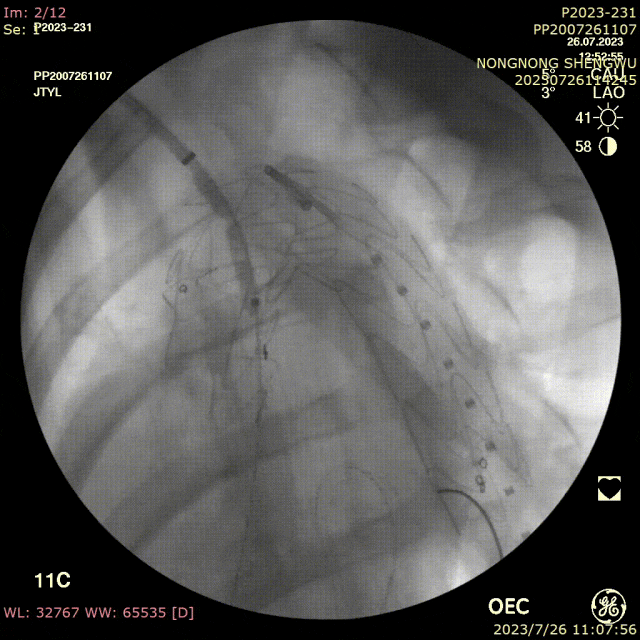

手术过程:

全麻下双上肢穿刺,右股动脉切开,左上肢路径造影,右上肢进保护性导丝,对支架预开窗后植入升主,因破口较大,支架近端掉入破口,远端扭转遮蔽左颈总动脉及头臂干,窗口对破口,再次植入一枚38-80支架,封住近端破口后,以8*60支架开放右侧头臂干,6*10人工血管行右锁骨下-左颈总搭桥,取颈前静脉行左椎动脉-人工血管搭桥,之后造影,头臂动脉均通常,术后约2小时患者清醒。